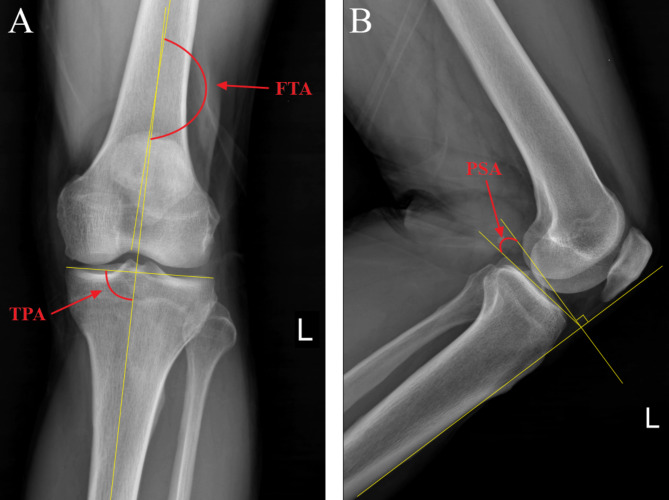

Every patient underwent reviews at one and three months following the surgery, followed by reviews every three months and subsequently, annually after the completion of fracture healing. These follow-up visits involved medical history interviews, physical examinations, and radiographs of the affected knee joint. Clinical data of patients, such as operation time, intraoperative blood loss, intraoperative fluoroscopy shoots, hospital stay, and fracture union time were collected. The follow-up time at the point of fracture healing was recorded as the fracture union time. Radiographs were taken immediately after surgery and at the 12 months after surgery, to measure and record the tibiofemoral angle (FTA), tibial plateau angle (TPA), and posterolateral slope angle (PSA) [16], as seen in Fig. 1. Mal-reduction was defined as intra-articular step-off exceeding 2 mm; TPA ≥ 95°; PSA ≥ 95° or ≤-5° [17]. The quality of fracture reduction was evaluated using Rasmussen’s anatomical score [18]. Additionally, the range of motion (ROM), Hospital for Special Surgery (HSS) score [19], and Rasmussen’s functional score [18] at 12 months follow-up were measured to evaluate knee function. Primary and secondary outcomes, including fracture union and fracture complications such as infections, traumatic osteoarthritis, delayed union, malunion, and nonunion were assessed based on standard clinical and radiological criteria.

Fig. 1.

Schematic diagram of radiographic parameters of tibial plateau. (A) The FTA and TPA on anteroposterior X-ray. FTA is the lateral angle between the anatomical axes of the femur and tibia, TPA is the medial angle between the tangential line of the tibial plateau and the anatomical axis of the tibia. (B) The PSA on lateral X-ray. PSA is the lateral tibial plateau line and the perpendicular line of the anterior tibial cortex